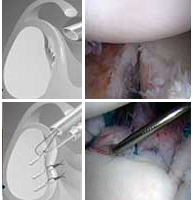

El tratamiento inicial es conservador, pero si este fracasa se produce una luxación recidivante yse tendrá que recurrir a la cirugía. En deportistas jóvenes se puede realizar la reparación quirúrgica tras la primera luxación. Se reparan las lesiones de los ligamentos dañados con tornillos y suturas que se implantan por vía artroscópica. Posteriormente se realiza rehabilitación.

En la actualidad los resultados de la reparación artroscópica son similares a la cirugía convencional (95%), con un postoperatorio mas confortable y con una mejor movilidad final del hombro.